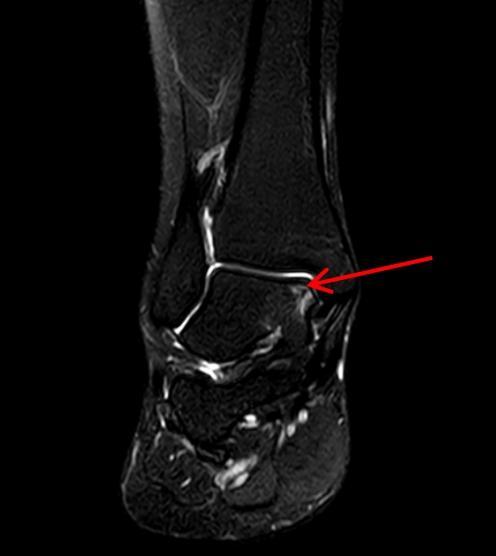

2023年8月6日,她经人介绍来到湖南省人民医院骨关节与运动医学科王靖主任医师处就诊,核磁共振检查显示:右侧踝关节内侧距骨软骨损伤,随即因“右踝距骨剥脱性骨软骨炎”将她收入关节与运动医学科病房。

▲术前MRI可见:距骨软骨损伤,软骨下骨碎片分离